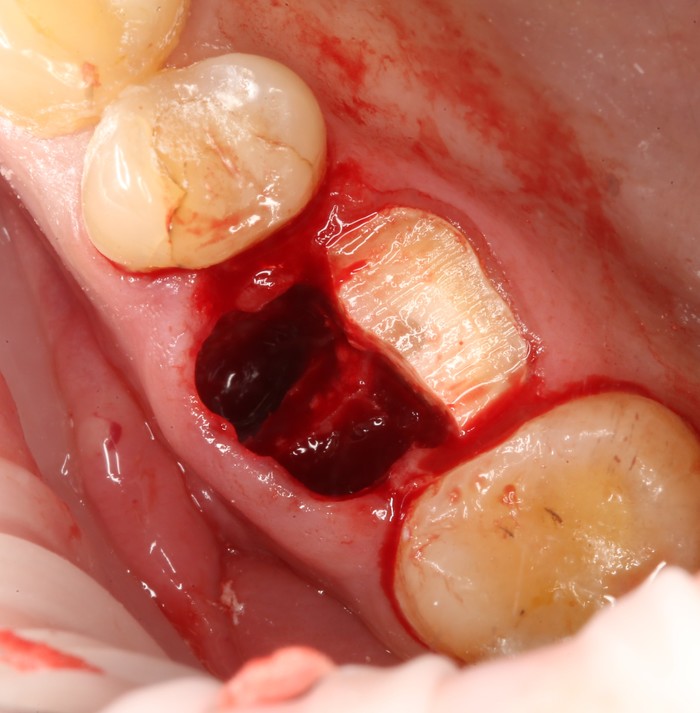

Выкрутили абатмент:

Установлена заглушка, которая закрывает шахту имплантата.

Теперь необходимо выждать около 2-х месяцев для того, чтобы десна восстановилась (Пациентка это время ходила со специальной капой, которая имитирует наличие зуба).

Далее проведена пластика десны, снова два месяца ожиданий и установка временной коронки: